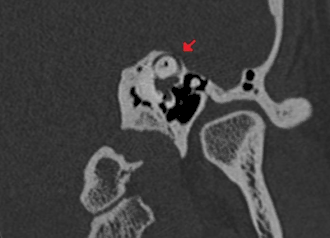

- La déhiscence osseuse peut être mise en évidence par un scanner des rochers en coupes fines. L'anomalie est au mieux visualisée sur les reconstructions coronales obliques dans le plan du canal semi-circulaire supérieur (plan de Pöschl)[2],[7]. Le défect osseux est en général supérieur à 3 mm et peut atteindre 6 à 7 mm[7]. L'importance de la déhiscence est corrélée à l'intensité des symptômes[8]. Des séquences d'imagerie par résonance magnétique de haute résolution fortement pondérées en T2 peuvent également mettre en évidence la déhiscence[2].